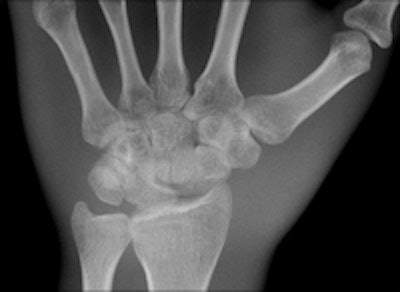

Two images of a hand phantom obtained using different equipment: Fuji's CR system and DRX-1 from Carestream. All images courtesy of Dr. Thomas Lehnert.

A third image of a hand phantom obtained using DR9500 from Carestream.Identical in size to a standard CR cassette, the detector can be inserted into an existing wall stand or table Bucky and used in combination with existing x-ray generators from a number of original equipment manufacturers, presenting an attractive option for modest-budget facilities. The flexibility of the portable detector provides great advantages in time-critical environments where an x-ray image can now be captured and viewed in less than six seconds, he explained.